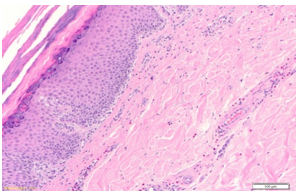

The blisters were not painful, but he did have some itching. He denied fever, chills, sore throat, cough, diarrhea or night sweats. He also denied recent ingestion of new medications, sick contacts, similar rashes in family members, dietary change, exposure to chemicals, or tick or mosquito bites. On presentation, he was afebrile and hemodynamically stable. Vitals were: Blood Pressure 106/76 mm of Hg, Heart rate 90 beats per minute, Respiratory rate 20 per minute, and Temperature was 97.2F. Notable labs included WBC 6.5k, Hgb 10.1, Hct 31.3, Plt 165k, Na 139, K 4.3, BUN 13.1, and Cr 1.56 (baseline 1.4-1.5), CRP 18.88, and ESR 29. HIV, RPR and Hepatitis serology were nonreactive. Procalcitonin was 0.07. Autoimmune screen including ANA screen, Rheumatoid factor, and Anti-CCP IgG antibody was all negative. Immunoglobulin levels except IgG subclass 4 were all within normal limits. IgG subclass 4 was elevated at 338. Herpes simplex virus type 1 and 2 DNA was not detectable. Dermatology team performed a biopsy of the bulla. Pathology reported as leukocytoclastic vasculitis and features suggestive of bullous pemphigoid or bullous drug eruption (Figure 4-6) and the patient was started on dexamethasone.

Figure 4: Punch biopsy of skin with epidermis showing hyperkeratosis and minimal spongiosis. In the superficial dermis, there is a mild mixed perivascular infiltrate. (Hematoxylin & Eosin stain, magnification 100X).

Figure 5: Dermal mixed superficial perivascular composed of neutrophils, eosinophils, and lymphocytes are seen. A fibrin thrombus is seen. Nuclear dust is also seen. Other features characteristic for leukocytoclastic vasculitis (e.g., fibrinoid vascular necrosis or extravasated red blood cells are not prominent. (Hematoxylin & Eosin stain, magnification 400X).